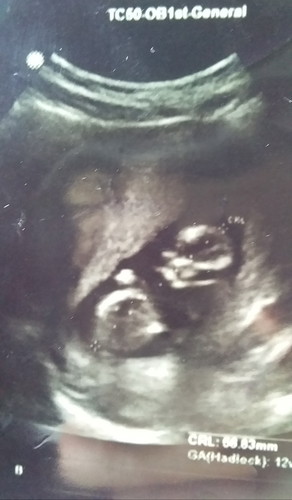

Bund mau tanyaa kemarin waktu bulan puasa aku USG kandungan, katanya janinnya uda 3 bulan, apa kahh bentukk janin itu yg di gambar USG itu uda 3 bulan atau blumm yaa soalnya dokter lain ada yang bilang 2 bulan jadi aku bingung nih bund, aku jugaa mau nanyaa itu janinnya kembar atau bukann yaah soalnya kemarin waktu USG dokter gak ada bilangg kembar, dan menurut penglihatan saya dan suami saya janinnya macem dua, mohonn jawabannya bunda" ?

Klo menurut ak ya bun itu 1 janin bun..itu yg dilingkarin kepala sama bagian kaki bun..klo ada 2 janin, hrs ada 2 kantong rahim bun..ga usah bingung bun, alatnya dokter jaman skrg ud canggih..klo msh penasaran nnti di usg lg aja..hehe yang penting jaga si debay sehat ya bun ๐

1 janin, ud dititik" sama dokternya untuk nentuin panjang bayi dr kepala - kaki. usianya tertulis d bwh itu bun, 12 weeks. dpt angka 12 weeks y dari panjang yg sdh diukur dokter tsb

Itu bisa 1 janin Bun.. 1 nya LG itu plasenta atau apa gtu. Q jg dlu gtu Bun.. Kalau soal umur khmlan brp atau mau jls bs cb usg lagi d tempat lain

1 janin aja. Kalo kembar biasanya kantongnya juga 2. Dan itu udah jelas janin cuma 1 yg digaris diukur panjang. Usianya 12w kelihatan dari GA

Ini janin sya wktu usg 3 bln bund... Dn kyk nya yg di bawah itu plsenta nya deh... Semoga sht trus ya bunda dan calon debay nyaa

Biasanya dokter mengetahui kembar atau tidak nya dr kantong ketuban melalui oemeriksaan usg, bisa jg dr suara detak jantungnya.

USG ulang aja bund bulan depan di dokter yang berbeda. Kalo saya lihatnya cuma satu janin sih bund. hehehe

sepertinya it 1 bun. yg 1 lagi plasenta nya.. tapi mgkn nnt bisa usg lagi

Iya itu 1 bund, yg putih tebel atasnya itu plasenta klo ga Salah